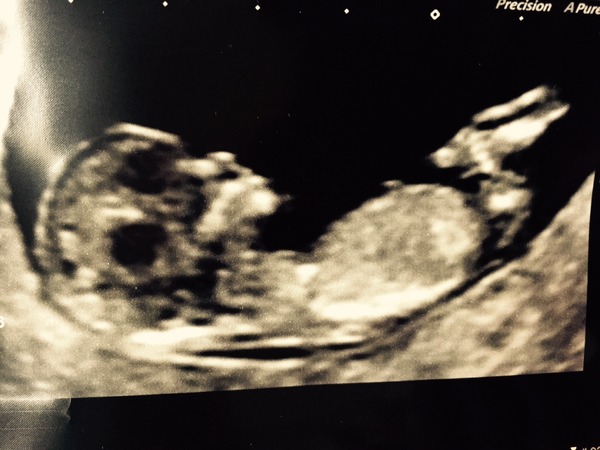

Oh thanks you girls! It went beautifully, the so I graphed and staff were so lovely, patient and sweet. Thank goodness for our brilliant NHS.

The babe was doing all sorts of yoga. It did downward dog, upward dog and a completely perfect bridge pose. Saw lots of bum shots. To me it looked like a girl based on the famous nub theory.

Nuchal measurement is 1.3 which they said looks perfect but obviously won't know till Downs bloods come back.

Here are the photos grabbed when it was not moving, which was really rare!

Can't wait to see others!!

Great scan pic focus!

How wonderful Focus, lovely pic! Can't wait til mine on Monday! Will have to try out the nub theory.

Wow, well done on the scan pics, how brilliant! Flowers

Loving all the scan pictures, my appointment is two weeks away cant wait!